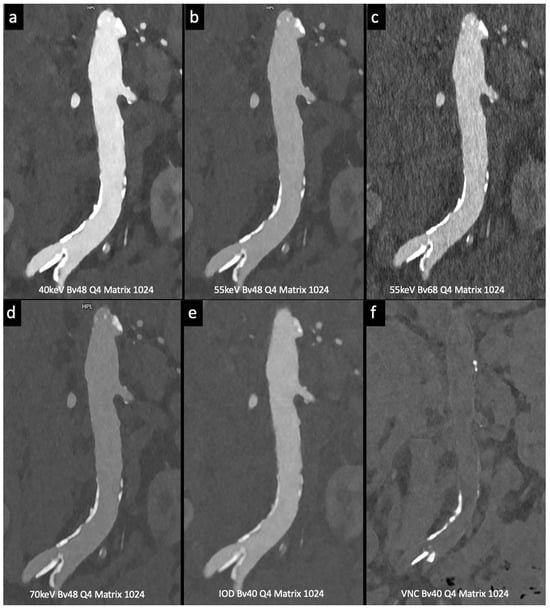

Figure 3. Comparison of image quality with photon-counting CT and standard contrast media. Abdominal aortic lumen with wall calcification axial images. High Resolution images (Matrix 1024 × 1024) with different reconstruction kernels (window level W2000, C700): 40 keV Kernel Bv48, Q4 (a); 55 keV Kernel Bv48, Q4 (b); 55 keV Kernel Bv68, Q4 (c); 70 keV Kernel Bv48, Q4 (d); Iodine map reconstruction, kernel Bv40, Q4 (e); Virtual Non-Contrast VCN reconstruction (f); 3D-Cinematic Rendering of the abdominal aorta (g). Department of Radiology, Fondazione Toscana Gabriele Monasterio, Pisa, Italy.

Figure 4. Comparison of image quality with photon-counting CT and standard contrast media. Abdominal aortic lumen with wall calcification coronal images. High Resolution images (Matrix 1024 × 1024) with different reconstruction kernels (window level W2000, C700): 40 keV Kernel Bv48, Q4 (a); 55 keV Kernel Bv48, Q4 (b); 55 keV Kernel Bv68, Q4 (c); 70 keV Kernel Bv48, Q4 (d); Iodine map reconstruction, kernel Bv40, Q4 (e); Virtual Non Contrast VCN reconstruction (f). Department of Radiology, Fondazione Toscana Gabriele Monasterio, Pisa, Italy.